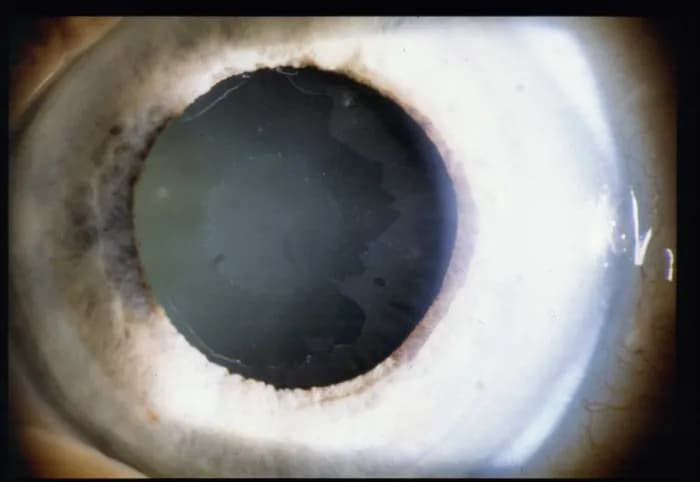

Jaskra barwnikowa to poważna choroba oczu, która może prowadzić do postępujących zaburzeń widzenia. Rozpoznanie jej objawów jest kluczowe dla zachowania zdrowia oczu. Wczesne zauważenie symptomów, takich jak ubytek w polu widzenia, może znacząco wpłynąć na jakość życia pacjenta. Osoby z jaskrą barwnikową mogą doświadczać trudności w wykonywaniu codziennych czynności, co podkreśla znaczenie świadomości na temat tej choroby.

Objawy jaskry barwnikowej są często subtelne, co sprawia, że ich rozpoznanie bywa wyzwaniem. Jednakże, ich wczesne zauważenie i zrozumienie może prowadzić do szybszej interwencji medycznej. Dlatego tak ważne jest, aby każdy był świadomy potencjalnych objawów jaskry barwnikowej i ich wpływu na codzienne życie. W następnych sekcjach omówimy konkretne objawy tej choroby oraz ich znaczenie dla funkcjonowania wzroku.

Ubytki w polu widzenia to jeden z pierwszych i najważniejszych objawów jaskry barwnikowej. Osoby z tym schorzeniem mogą zauważać, że ich widzenie staje się coraz bardziej ograniczone, zwłaszcza w obszarach peryferyjnych. Przykładowo, mogą mieć trudności z dostrzeganiem przedmiotów znajdujących się na bokach, co może prowadzić do niebezpiecznych sytuacji, zwłaszcza podczas prowadzenia pojazdów. Wczesne rozpoznanie tego objawu jest kluczowe, ponieważ może pomóc w uniknięciu dalszej utraty wzroku.

Zmiany w percepcji kolorów to kolejny symptom, który może wystąpić u osób z jaskrą barwnikową. Pacjenci mogą zauważać, że kolory wydają się mniej intensywne lub zmieniają swoją barwę. Tego rodzaju zmiany mogą wskazywać na postępujące uszkodzenie nerwu wzrokowego i wskazywać na zaawansowanie choroby. Właściwe rozpoznanie tych objawów jest kluczowe, ponieważ może to pomóc w monitorowaniu stanu zdrowia oczu oraz w podejmowaniu decyzji dotyczących ewentualnego leczenia. Objawy jaskry barwnikowej, takie jak zmiany w percepcji kolorów, powinny być zawsze zgłaszane lekarzowi, aby mogły być odpowiednio ocenione.